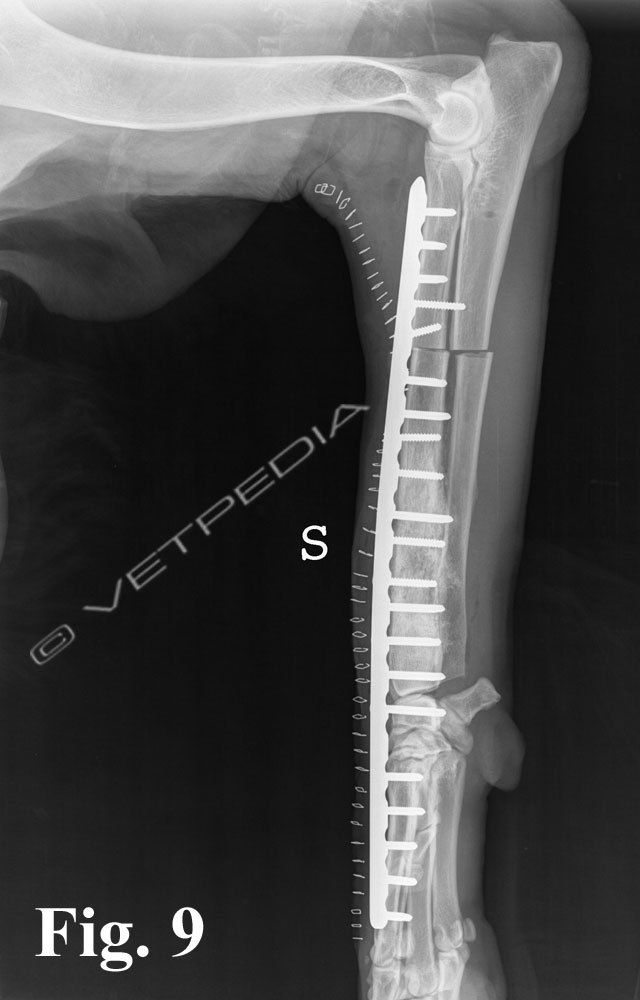

{{/_source.additionalInfo}}L'osteosarcoma è un tumore che può svilupparsi sia nel cane che nel gatto.Nel cane rappresenta l’85-98% dei tumori ossei in questa specie animale (Liptak et al., 2004b; Dernell et al., 2007). Sono più frequenti le localizzazioni appendicolari (75%) ma può anche svilupparsi a carico dello scheletro assiale (24%) e occasionalmente in sedi e